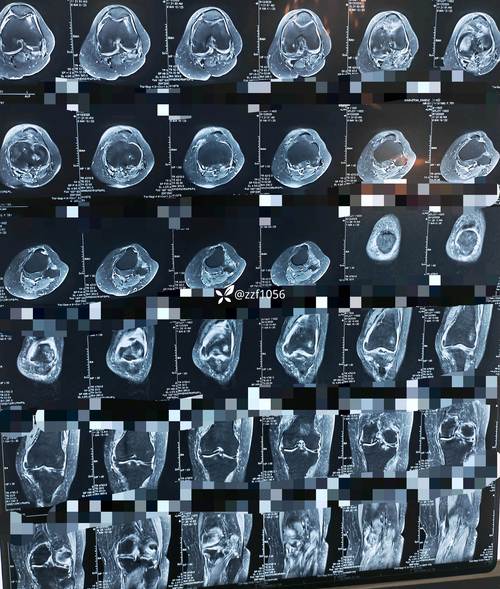

5. 关节积液

MRI可以非常敏感地检测到关节腔内的异常积液,这也是关节炎症活动的一个指标。

核磁共振相比X光片的优势

特性 X光片 核磁共振

成像原理 显示骨骼的密度和结构 显示水分子在组织中的分布,对软组织极敏感

早期诊断 不敏感,当骨侵蚀达到一定程度(通常丢失20-30%的骨量)才能被发现。 非常敏感,可以在出现骨侵蚀之前就发现滑膜炎和骨髓水肿。

评估范围 主要看骨骼,对滑膜、肌腱等软组织基本无效。 全面评估骨骼、软骨、滑膜、肌腱、韧带、神经等所有结构。

评估活动性 只能显示陈旧性的结构性损伤(如骨侵蚀),无法反映当前炎症活动。 可以通过对比剂增强,直接显示正在活动的炎症(如滑膜强化)。

辐射 有电离辐射。 无电离辐射,非常安全。